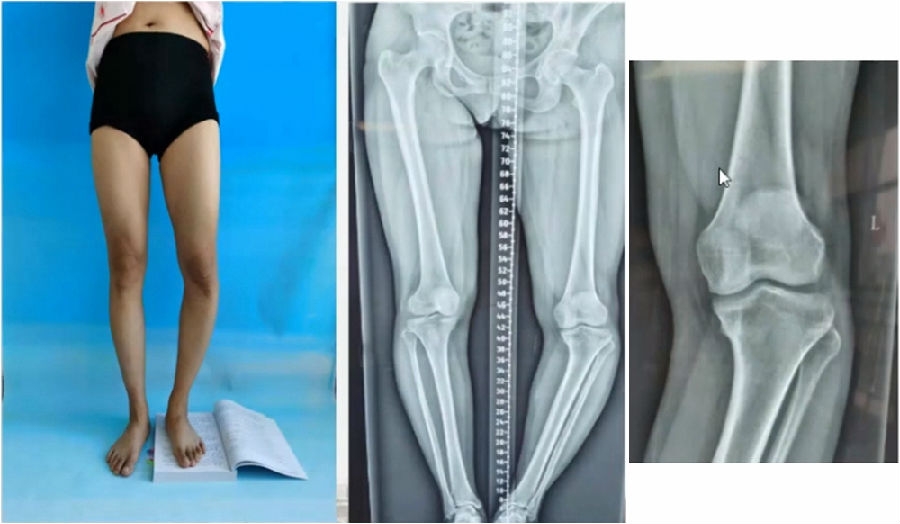

典型病例,女性,35岁,农民,左膝内翻、短缩、内旋。

术前

泰勒外固定架缓慢矫正短缩、内翻、前弓、内旋。

术中

该患者截骨后,做MAD矫正,目标MAD=0。患者术后1个月即达到设计的效果。

术后1个月

典型病例2,男性,52岁,双膝疼痛,低磷佝偻病,复合畸形。

股骨畸形即时矫正,胫骨畸形缓慢矫正。

手术前后对比

手术前后外观